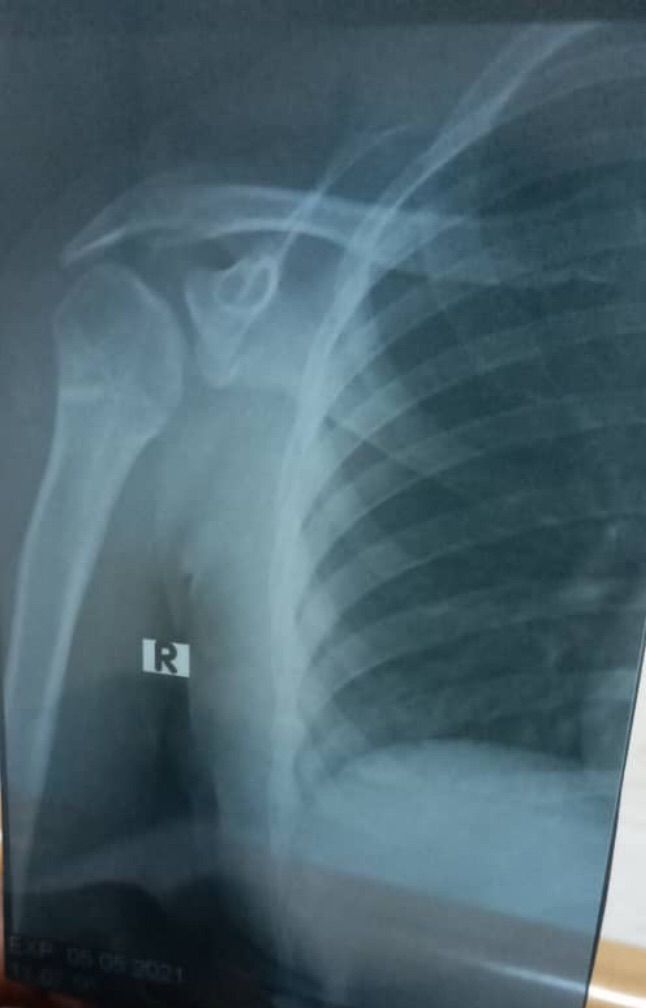

15 year old women what’s diagnosis and treatment

Shoulder dislocation